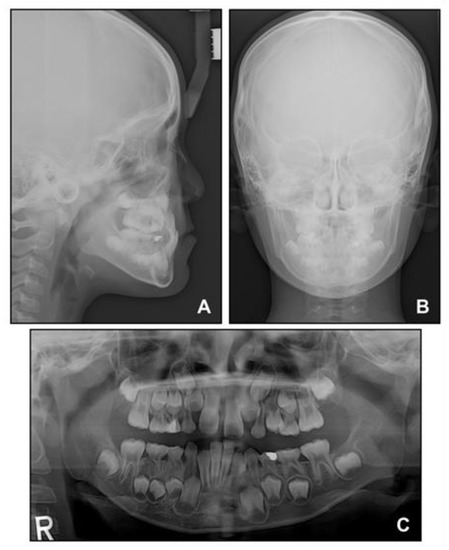

Lateral cephalometric analysis showed an angle of the lines connecting the sella, nasion, and point A (SNA) of 75.4°, an angle of the lines connecting the sella, nasion, and point B (SNB) of 75.7°, and angle of the lines connecting point A, nasion, and point B (ANB) of −0.3° (Table 1 and Figure 3). Both maxillary and mandibular incisors were lingually inclined, and the upper lip was retruded with respect to the Ricketts’ esthetic line. In posteroanterior cephalometric analysis, there were no noticeable asymmetric features. A panoramic radiograph showed that a supernumerary tooth was impacted in the right mandibular premolar area. There were no pathologic osseous findings in the gingival hypertrophic area of the anterior mandible.

When the patient reached 13 years of age, he claimed that his teeth were still not fitting well. He showed a mild chin point deviation toward the right side, and severe lip canting while smiling was still present. The lateral facial profile was maintained favorably after the phase 1 treatment, but the Becker’s nevus area on the right cheek through the upper neck was more prominent, with hypertrichosis (Figure 7 and Figure 8). Intraorally, all permanent teeth except the second molars had successfully erupted; however, the hypertrophic region in the anterior mandible was still present. Therefore, he showed severe canting of mandibular anterior teeth with a 1 mm deviation of the apical base midline of the mandibular dentition toward the right side.

At this point, we noticed that the nevus, facial asymmetry, lip canting, and hypertrophy of alveolar bone occurred in the same area. Taking into consideration these symptoms, we suggested the presence of “Becker’s nevus syndrome” for the simultaneous occurrence of Becker’s nevus and other systemic anomalies. We interviewed the patient, and he informed us that he had been recently diagnosed with scoliosis by an orthopedist (Figure 8D). Fortunately, the severity of the scoliosis was incipient to moderate, with no need for active treatment but only a need for observation.

Figure 3. Pre-treatment radiographs: (A) Lateral cephalogram; (B) Posteroanterior cephalogram; (C) Panoramic radiograph.

Figure 8. Radiographs before phase 2 treatment: (A) Lateral cephalogram; (B) Posteroanterior cephalogram; (C) Panoramic radiograph; (D) Standing anteroposterior radiograph of spine showing scoliosis.